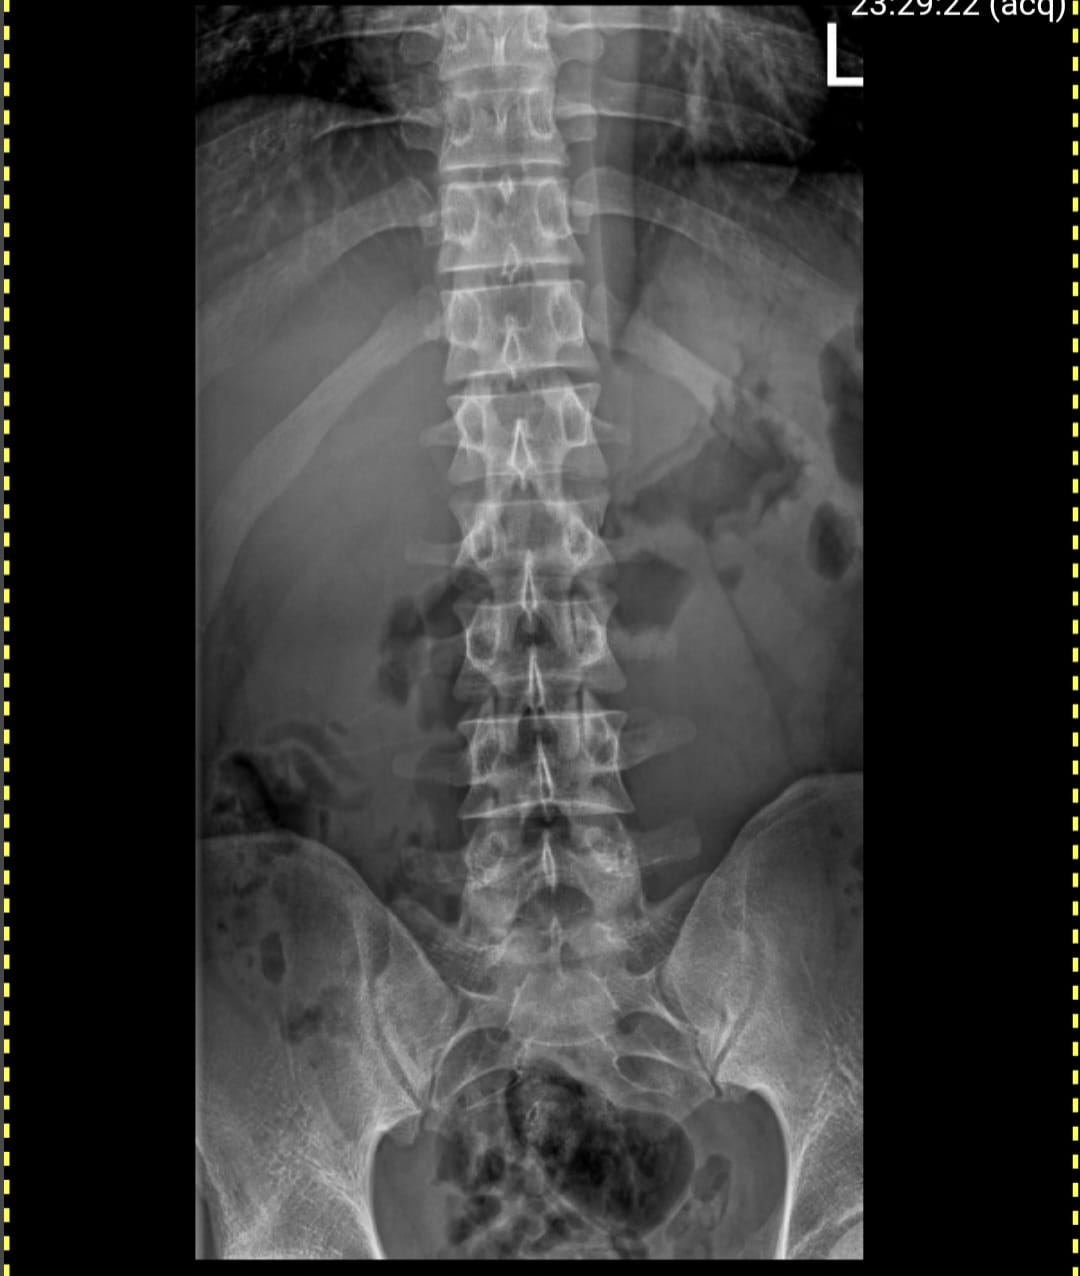

Spinal X-rays

Specialized digital X-rays for the Cervical, Thoracic, and Lumbar spine regions. We provide precise imaging for back pain, posture evaluation, and Road Accident Fund (RAF) radiological reports.